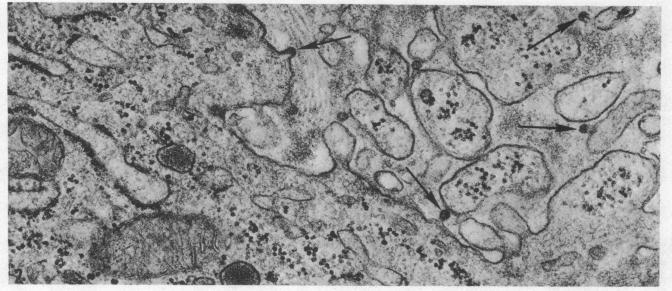

An electron microscopic study of virus particles in rhesus monkey placenta.

Examination of chorionic villi from rhesus monkey placenta revealed the presence of C-type virus particles budding from syncytial trophoblast, pericytes, Hofbauer cells, and mesenchyme. In addition, particles, were found budding from cells of the cytotrophoblastic cell column and decidual basalis. They measured 30 nm in diameter, had a dense central core, surrounded by a narrow, electron-lucent zone, and were enclosed by an outer unit membrane.